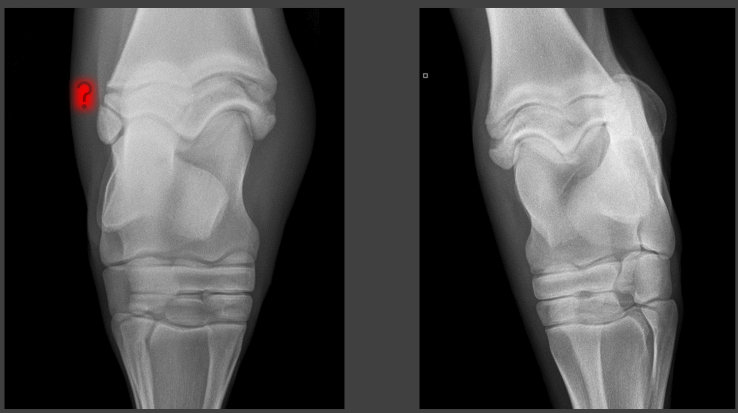

A

tarsal OCD fragment